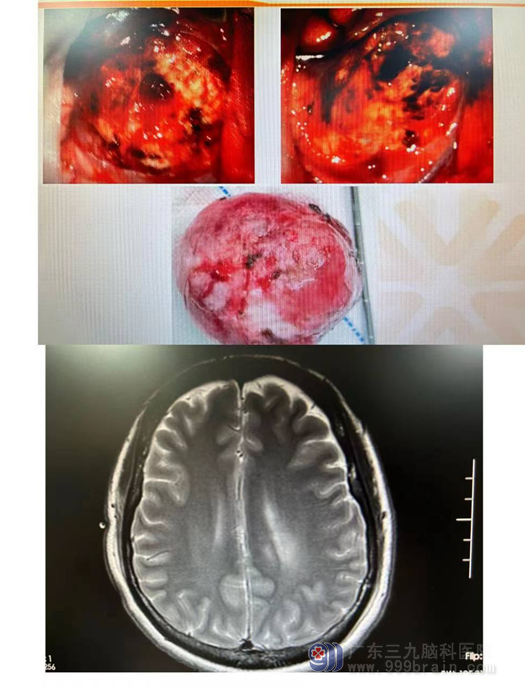

欧阳辉教授带领神经外十科医生团队,对患者进行详细的检查,并为患者制定了手术方案,在医生的沟通下,患者及其家属同意手术治疗。我科精准实施手术:采用全麻下行“左侧额部镰窦旁占位性病变切除+硬脑膜修补术+颅骨成型术”。在外十科手术团队、麻醉科、手术室的团结合作下,完整摘除了一颗“大荔枝”一样的肿瘤,术中、术后都很成功。

术后朱女士很快神志清醒,言语对答切题,头部切口愈合良好,三天后即可下床活动,头部外形也完全的恢复了正常。